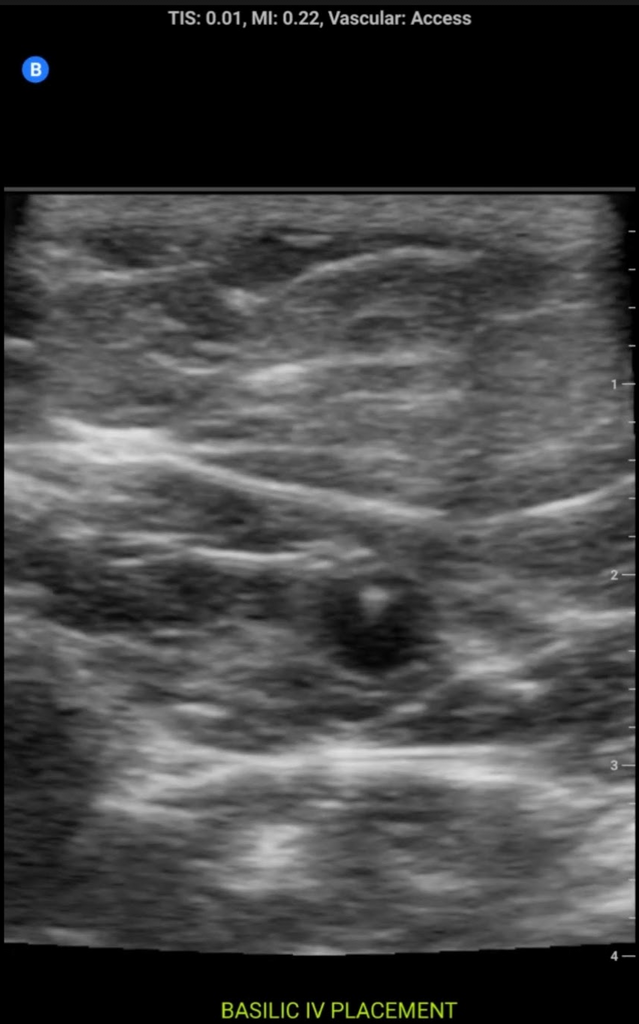

Some sample images below:

screenshot.177.pngscreenshot.178.pngscreenshot.180.pngscreenshot.179.png

View attachment 328368View attachment 328369View attachment 328371View attachment 328372